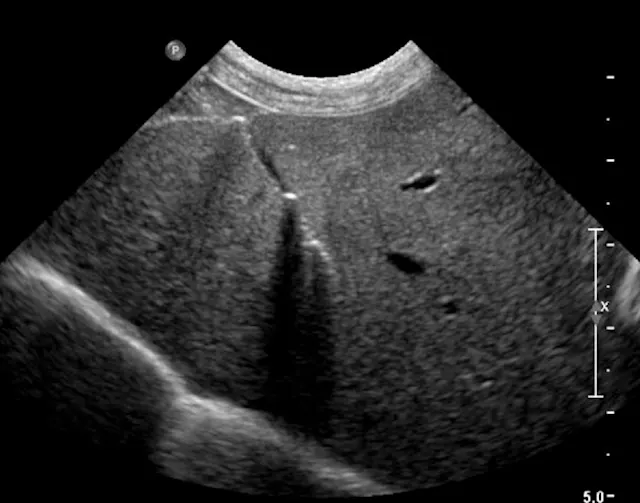

Biopsy needle tract within the patient after firing and just before removing the biopsy device (B). Post-biopsy hemorrhage often collects between hepatic lobes as seen in this image (white arrow heads) (C). The echogenic fluid represents acute hemorrhage. Color flow Doppler post-biopsy ensures there is no persistent hemorrhage in the peritoneal space (D). Power Doppler imaging is the most sensitive form of Doppler to detect the presence or absence of blood flow.

Step 8: Inspect for Hemorrhage

Every time a biopsy is made, the site should be inspected for evidence of hemorrhage. Hemorrhage will often collect around and between liver lobes as seen in 5C between the arrowheads. Color (or power) Doppler ultrasound may help visualize active bleeding as seen in 5D. Once the patient is no longer bleeding, the patient can be recovered. Observe the patient closely in the postoperative period for clinical evidence of blood loss. Serial ultrasound examinations may be beneficial for discovering progression hemorrhage. If the patient continues to bleed, a blood transfusion may be needed. It is usually beneficial to obtain packed-cell volume readings at 15 and 45 minutes post-biopsy to ensure that active bleeding has stopped. An external elastic belly wrap can be helpful in preventing further hemorrhage.